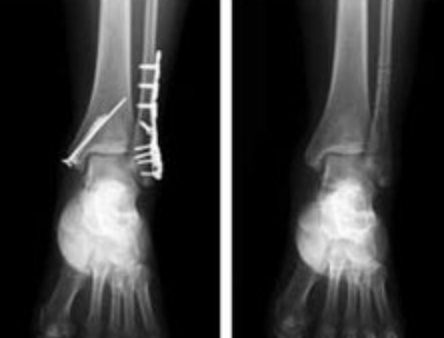

하지만 지나간 과거는 지워지는 것이 아니지요.

뼈가 부러졌으면 부러진 흔적은 우리 몸 속에 영원히 남는 법이에요.

그렇지만 뼈가 부러진 곳을 더 단단하게 만들어줄 수는 있지요.

몸은 특별하게 아픈 부분에 더 많은 영양분을 주려는 특성이 있기 때문이죠.